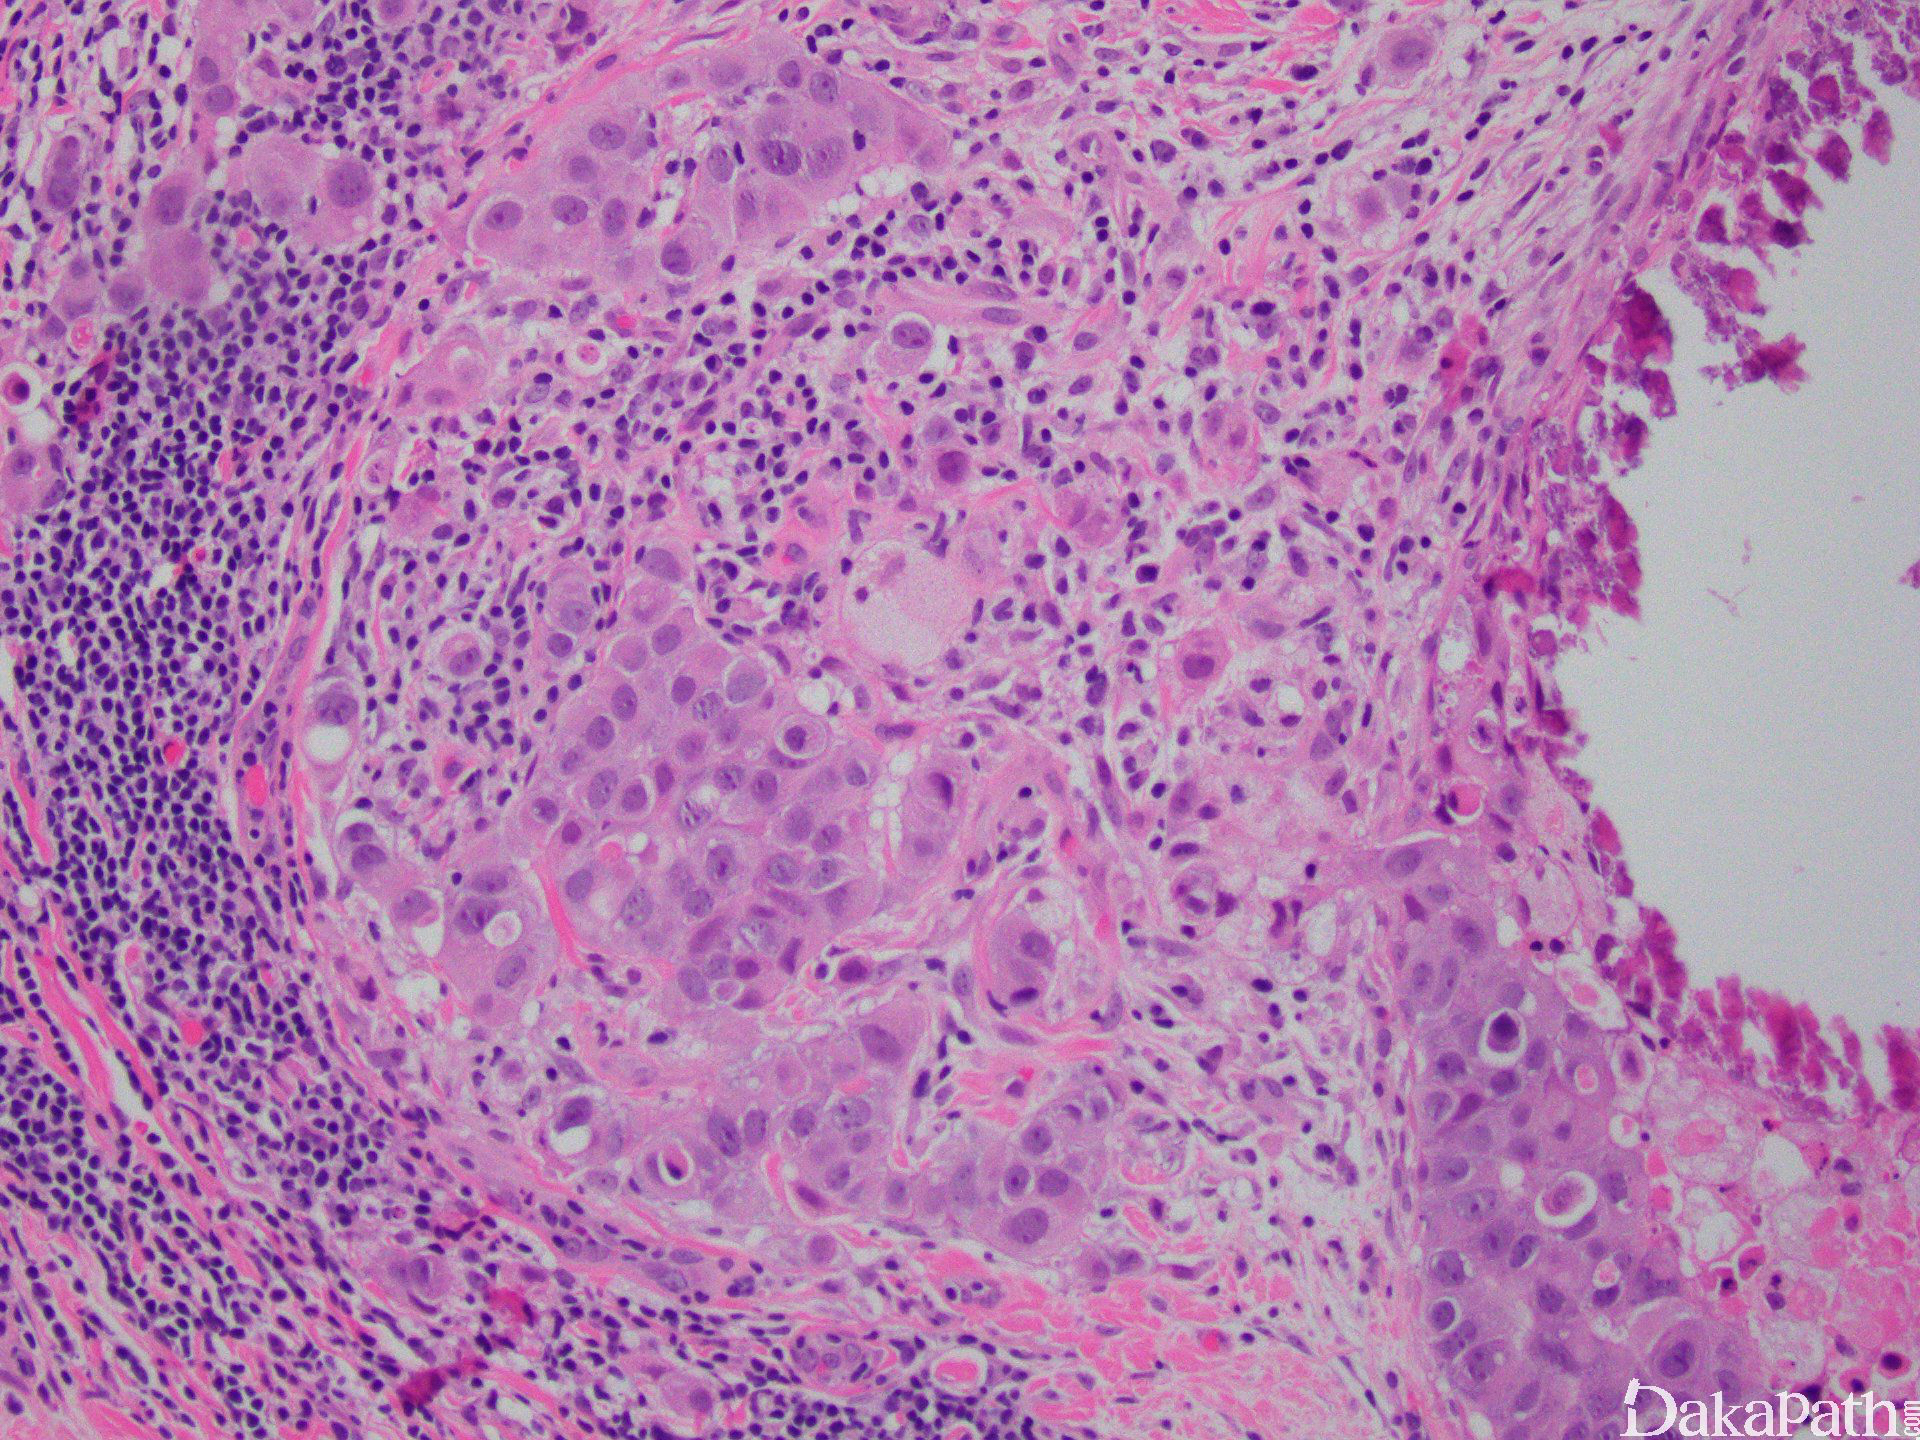

以原位癌为主伴有 1 个或多个微小浸润灶,每个浸润灶最大径不超过 1mm。

肿瘤主体常为管内癌,少数为小叶原位癌;

导管周围或小叶间质肿瘤细胞浸润灶最大径不超过 1mm;

浸润灶周围常伴纤维母细胞增生、胶原化或炎细胞浸润;

浸润灶周围缺乏肌上皮及基底膜。